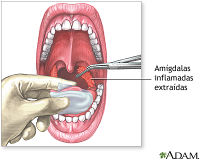

Amigdalectomía - EcuRed